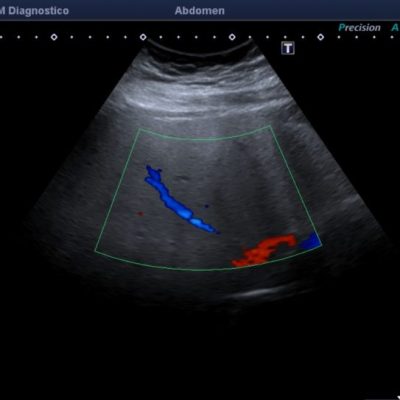

El médico de referencia le indica nueva ecografía de control, donde se observan múltiples y extensas lesiones focales hepáticas hiperecogénicas, redondeadas y confluentes, las cuales predominan en adyacencia a venas supra hepáticas, sin condicionar efecto de masa y sin alteración de la superficie hepática(fig. 1 y 2). Ante la valoración con Doppler color no presenta patrón de flujo peri ni intralesional y respeta el calibre de las venas supra hepáticas(fig. 3 y 4). Dada las características ecográficas se sospecha esteatosis focal multinodular confluente como principal diagnóstico presuntivo, siendo los diagnósticos diferenciales patologías de naturaleza infecciosa, tumoral o metastásica.